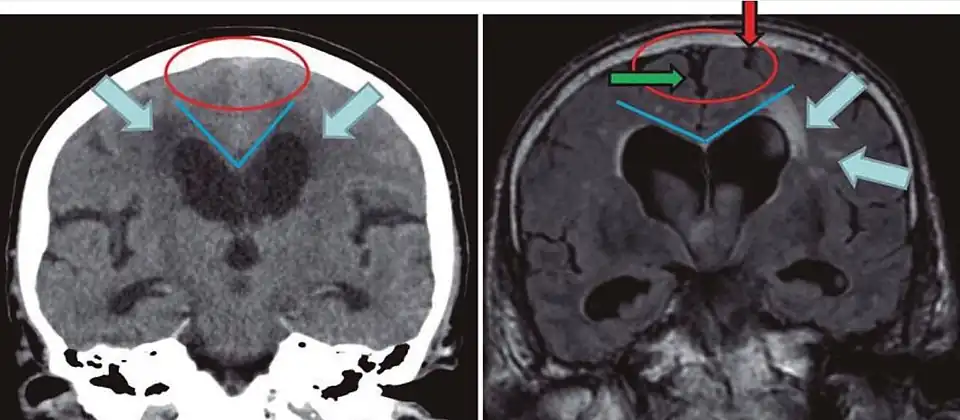

Typical imaging findings in normal pressure hydrocephalus versus brain atrophy.[21]

Normal pressure hydrocephalus Brain atrophy

Preferable projection Coronal plane at the level of the posterior commissure of the brain.

Modality in this example CT MRI

CSF spaces over the convexity near the vertex (red ellipse ) Narrowed convexity ("tight convexity") as well as medial cisterns Widened vertex (red arrow) and medial cisterns (green arrow)

Callosal angle (blue V) Acute angle Obtuse angle

Most likely cause of leucoaraiosis (periventricular signal alterations, blue arrows ) Transependymal cerebrospinal fluid diapedesis Vascular encephalopathy, in this case suggested by unilateral occurrence